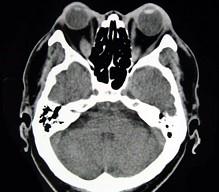

问题 女性50岁,消瘦、多饮多食,脖子粗大,双侧眼球突出,一年余,CT检查如图所示,应考虑为 ( )

选项 A、横纹肌肉瘤 B、眶部结核 C、甲状腺眼病 D、炎性假瘤 E、眼型格氏病

答案 C